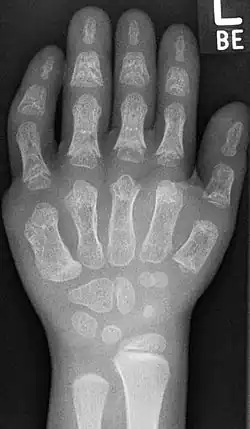

Die äußerlichen Hauptsymptome sind der Kleinwuchs, Thoraxdeformität mit verkürzten Rippen, die Polydaktylie, sowie hypo- oder dysplastische Fingernägel und Zähne. Die Polydaktylie ist an den Händen üblicherweise beidseitig, postaxial (Außen) auf der ulnaren Seite. Bei etwa 10 % der Patienten sind auch die Füße von der Polydaktylie betroffen. Häufig ist zwischen der Großzehe (Hallux) und der zweiten Zehe ein größerer Zwischenraum.[2] Die Extremitäten wirken meist plump. Die mesomele (mittlere Anteile, das heißt Unterarm beziehungsweise -schenkel) und akromele (distale Anteile, das heißt Finger beziehungsweise Zehen) Verkürzung der Gliedmaßen ist sehr häufig. Sehr oft können die Patienten die Hand nicht zu einer Faust ballen.[3][4]

Radiologische Kriterien sind:[14]

- Verkürzte Fingerglieder mit Zapfenepiphysen der Mittel- und Endphalangen

Häufig Hexadaktylie, Fusion von Handwurzelknochen (Os hamatum und Os capitatum) Häufig Radiusköpfchenluxation und Patellaluxation, postaxiale Polydaktylie[15].